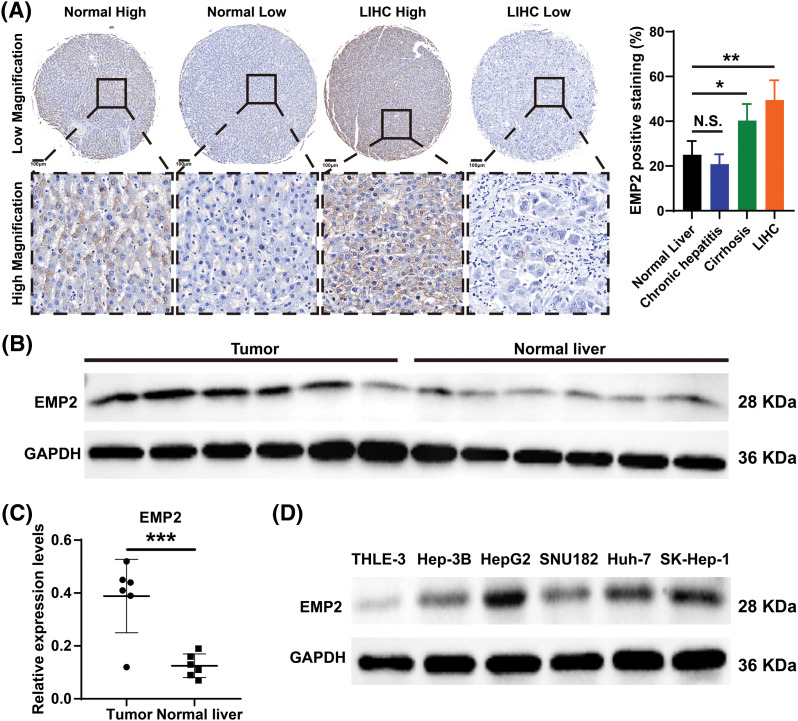

EMP2 promoted cellular autophagy and invasion in HCC cells

Immunohistochemical staining was performed to evaluate the expression level of EMP2 protein in liver disease tissue microarrays. HCC tissue exhibited a significantly higher positive rate of EMP2 compared to normal liver tissue. Furthermore, in HCC tissue, a higher level of EMP2 protein expression was associated with greater morphological heterogeneity and higher malignancy. The EMP2 positive stained ratio were around 20% in the normal liver and chronic hepatitis tissues, and over half of HCC tissue with high EMP2 staining (Figs. 4A and A1, Table A2). EMP2 was primarily localized in the cytoplasm, with minimal nuclear staining observed. The experimental results demonstrated an increasing trend in EMP2 protein expression as liver disease progressed from inflammation to liver cirrhosis and ultimately to HCC. Moreover, the expression level of EMP2 protein in HCC tissue positively correlated with the malignancy grade, indicating a significant role of EMP2 in the progression of liver diseases. To further validate these findings, six pairs of HCC tissues and matched adjacent normal liver tissues were collected. In five out of the six tissue samples, HCC tissues exhibited significantly higher levels of EMP2 expression compared to adjacent liver tissues. However, in one pair of tissues, the difference in EMP2 protein expression between HCC tissues and adjacent liver tissues was not sound (Figs. 4B–4D). In addition, the level of EMP2 protein expression was assessed in various liver or liver cancer cell lines. EMP2 protein expression was low in the normal liver epithelial cell line THLE-3. In contrast, the level of EMP2 protein expression was relatively high in five HCC cell lines (including Hep-3B, HepG2, SNU182, Huh-7, and SK-Hep-1).